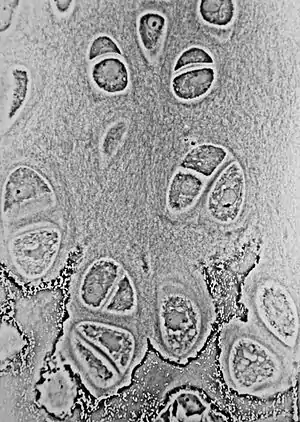

Light micrograph of an undecalcified epiphyseal plate that is displaying the hypertrophic zone with its typical chondrocytes, matrix and three zones: maturation (top), degenerative (middle) and provisional calcification (bottom). | |

The growth plate has a very specific morphology in having a zonal arrangement as follows:[8]

| Epiphyseal plate zone (from epiphysis to diaphysis) | Description |

| Zone of reserve | Quiescent chondrocytes are found at the epiphyseal end |

| Zone of proliferation | Chondrocytes undergo rapid mitosis under influence of growth hormone |

| Zone of maturation and hypertrophy | Chondrocytes stop mitosis, and begin to hypertrophy by accumulating glycogen, lipids, and alkaline phosphatase |

| Zone of calcification | Chondrocytes undergo apoptosis. Cartilagenous matrix begins to calcify. |

| Zone of ossification | Osteoclasts and osteoblasts from the diaphyseal side break down the calcified cartilage and replace with mineralized bone tissue. |